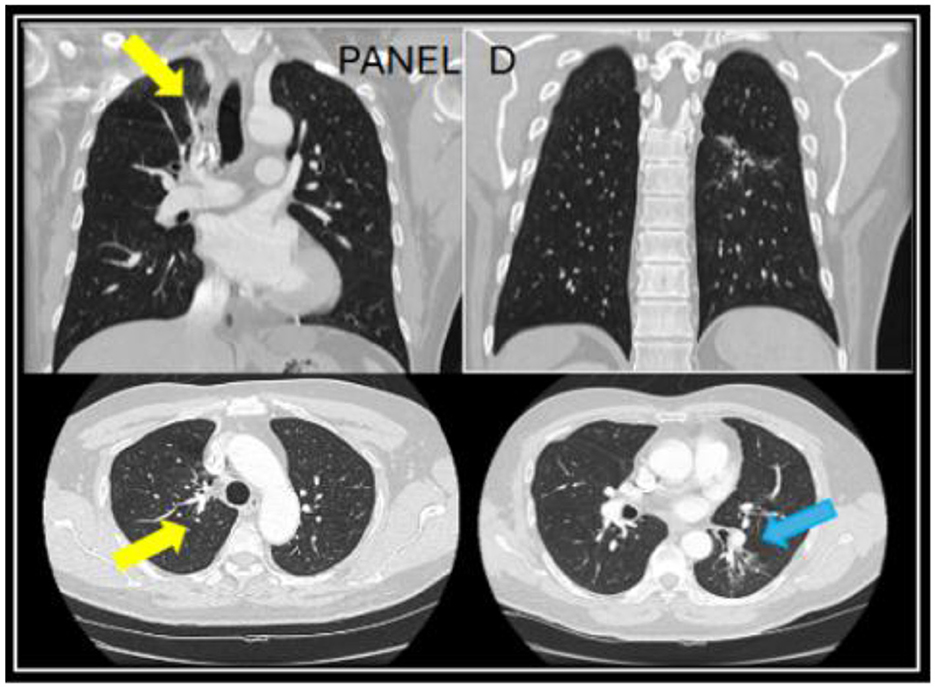

However, the patient expressed concerns about a new onset dry cough a year later. He was urged to present to the clinic for a clinical workup, but he did not follow up for 6 months. When he presented to the clinic, he continued to endorse persistent symptoms of dry cough and shortness of breath. A CT chest revealed a new right upper lobe infiltrate, and the patient's Coccidioides CF titer had spiked to 1:64 (Figure 2). Recognizing this as a relapse of pulmonary coccidioidomycosis, the patient was promptly restarted on itraconazole, which resulted in dramatic resolution of symptoms within 2 weeks. With initiation of itraconazole, the patient's ruxolitinib dose was again reduced to PO 5 mg BID. Follow-up testing showed a steady decline in CF titers to 1:4, confirming the effectiveness of continued antifungal therapy. Repeat CT imaging revealed resolution of right upper lobe infiltrate after 2 years of itraconazole use (Figure 3). At the time of publication of this paper, the patient has continued to maintain effective disease control on itraconazole and ruxolitinib and will continue with indefinite antifungal treatment.

Figure 3. A follow up CT chest done at year four while being on long-term itraconazole showed resolution of the right upper lung infiltrate (yellow arrows) and residual reticulated bronchiectasis in the left lower lobe [blue arrow in (D)].